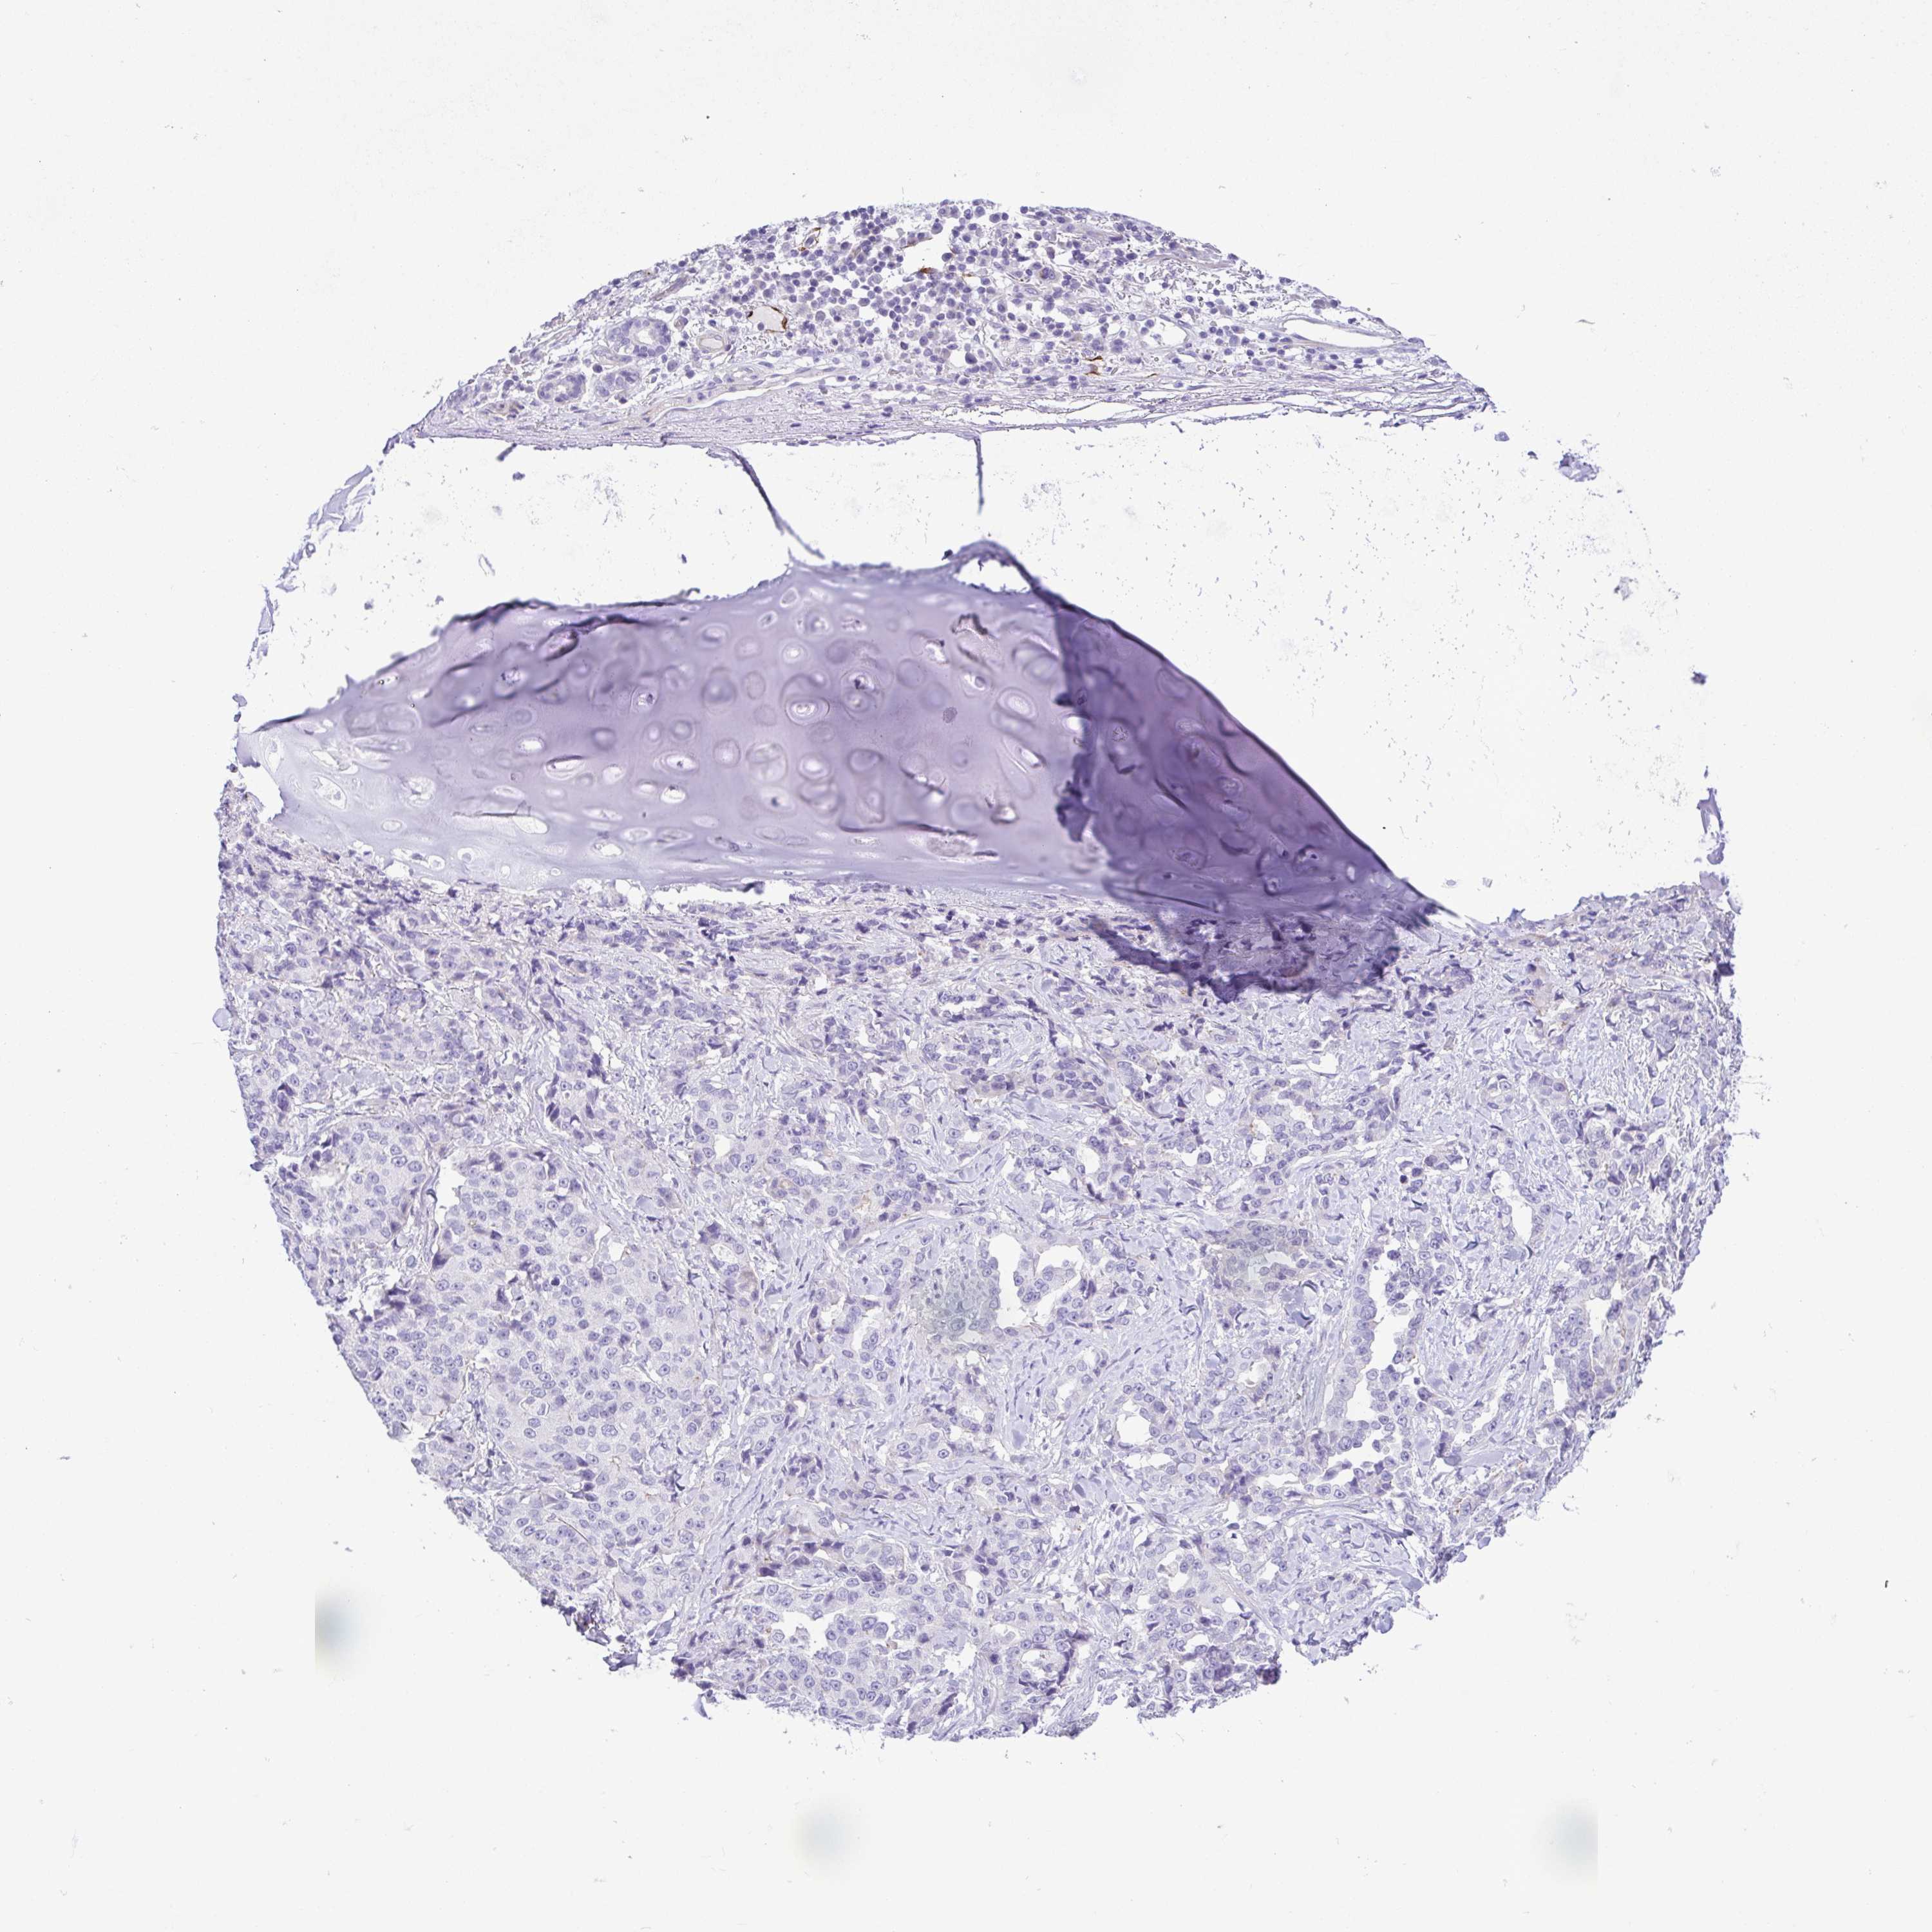

LUNG SQUAMOUS CELL CARCINOMA (TCGA) - Interactive survival scatter ploti

The Survival Scatter plot shows the clinical status (i.e. dead or alive) for all individuals in the patient cohort, based on the same data that underlies the corresponding Kaplan-Meier plots. Patients that are alive at last time for follow-up are shown in blue and patients who have died during the study are shown in red.

The x-axis shows the expression levels (FPKM) of the investigated gene in the tumor tissue at the time of diagnosis. The y-axis shows the follow-up time after diagnosis (years). Both axes are complimented with kernel density curves demonstrating the data density over the axes. The top density plot shows the expression levels (FPKM) distribution among dead (red) and alive patients (blue). The right density plot shows the data density of the survived years of dead patients with high and low expression levels respectively, stratified using the cutoff indicated by the vertical dashed line through the Survival Scatter plot. This cutoff is automatically defined based on the FPKM cutoff that minimizes the p-score. The cutoff can be changed by dragging the vertical line or by entering a cutoff value in the square labeled "Current cut-off".

Under the Survival Scatter plot the p-score landscape (black curve; left axis) is shown together with dead median separation (red curve; right axis). Dead median separation is the difference in median mRNA expression between patients who have died with high and low expression, respectively. It is calculated as follows: median FPKM expression of dead patients with high expression - median FPKM expression of dead patients with low expression. This is intended to aid the user in visually exploring custom cutoffs and the associated p-scores and dead median separation.

Individual patient data is displayed and can be filtered by clicking on one or more of the category buttons on the top of the page. Categories describing expression level and patient information include: high, low, alive, dead, female, male and tumor stages. The scale of the x-axis can be toggled between linear and log-scale by clicking on the "x log" button. Mouse-over function shows TCGA ID, patient information and mRNA expression (FPKM) for each patient.

& Survival analysisi

Kaplan-Meier plots summarize results from analysis of correlation between mRNA expression level and patient survival. Patients were divided based on level of expression into one of the two groups "low" (under cut off) or "high" (over cut off). X-axis shows time for survival (years) and y-axis shows the probability of survival, where 1.0 corresponds to 100 percent.

GPR182 is not prognostic in Lung Squamous Cell Carcinoma (TCGA)